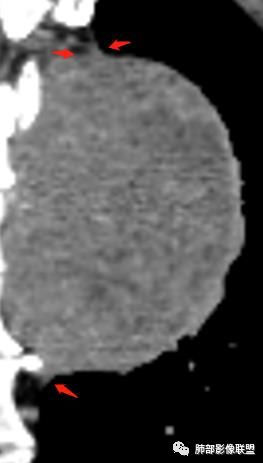

M-Imaging :有完整的壁

丽:有包膜

M-Imaging :

M-Imaging :包膜有强化

嗜酸性粒细胞:是包膜还是血管哦

平安是福:平扫31Hu,动脉期33–42Hu,静脉期,39–54Hu。

1.左上胸内脊柱旁半圆形肿块,质地坚实,密度比较均匀。

7.静脉期轻度强化,注意不是环形强化,亦未显示明确的“AB区”,神经鞘瘤与副节瘤亦未找到支持点。